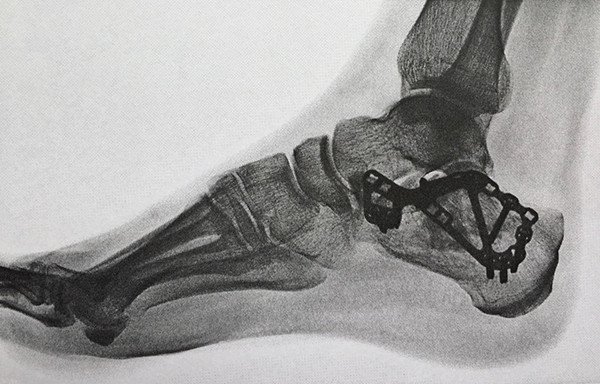

Vorstellung einer 32jährigen Patientin in unserer Sprechstunde, welche sich im Vorjahr nach einem Sturz von einer hohen Mauer eine Fraktur des Fersenbeines zugezogen hatte (Abb. 1 und 2). Auswärtig wurde diese durch eine Plattenosteosynthese versorgt (Abb. 3), der postoperative Verlauf gestaltete sich soweit komplikationslos.